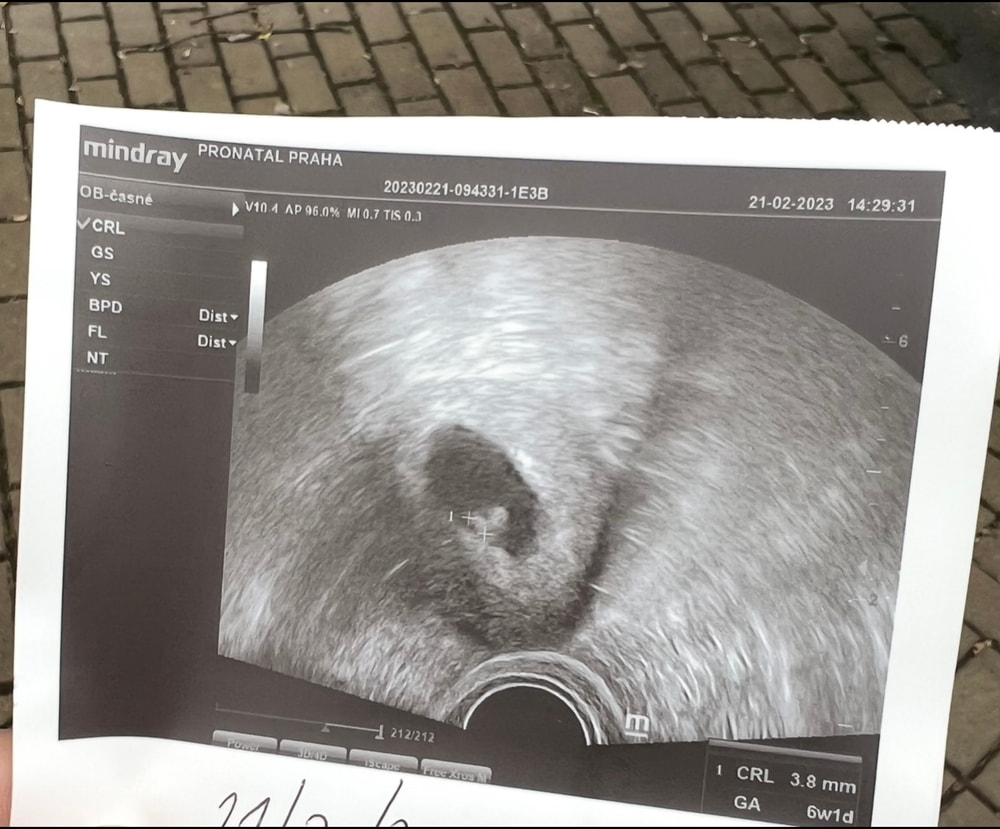

УЗИ 25ДПП

Пя 18мм, ктр 4,3, жм тоже около 4. Сердце на 25 дпп тоже не слушал, только пульсацию увидели и всё)

Это УЗИ на 26 ДПП , была видна пульсация😊 Изображение

Первое узи 20дпп Узи на 21 день после переноса